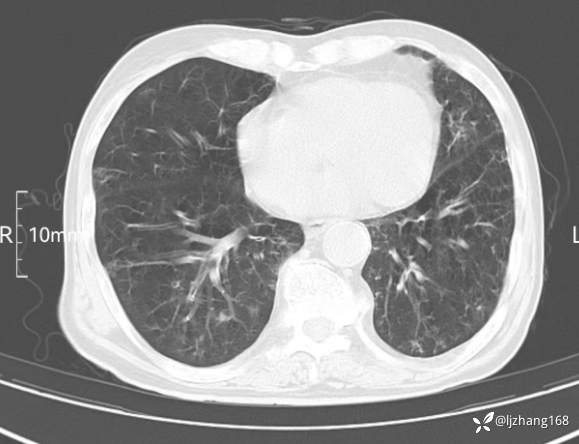

辅助检查:胸部CT:双肺肺气肿,间质性病变,血气分析:PH 7.413, PCO2 29.2mmHg, PO2,81.8mmHg,乳酸 3.3mmol/1,剩余碱-4.0mmol/1,HC03 18.8mmol/1。全血超敏C反应蛋白:超敏C反应蛋白 135.60 mg/L、 白细胞 14x19^9/L,中性粒细胞11.6x10^9/L。